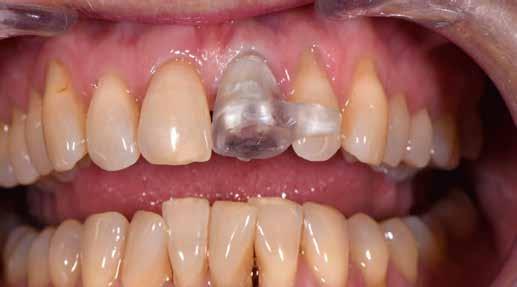

Előkezelés

2023 elején került behelyezésre a 21-es régióba egy Camlog Tissue Level implantátum, 4,3 mm átmérővel és 13 mm hosszal. Az eseménymentes gyógyulást követően az implantátum csontosodását a Periotest-eljárással ellenőriztük, majd hagyományos zárt kanalas lenyomatvétel után ideiglenes ellátás készült (2–4. képek).

építményhez gyári Camlog titánbázist használtunk, amit előzetesen befedtünk DCMhotbond fusio connect spray-vel. A titánbázis felületi kondicionálásához alkalmazott anyag kiváló, résmentes és tartós kötési alapot teremt a bázis és a rá készülő cirkon konstrukció között1. A cirkónium-dioxid egyedi felépítmény tervezését primer teleszkóp koronaként választottuk ki a CAD-szoftveres lehetőségek tárából. A felső mintát a beszórt titánbázissal ínymaszkkal és anélkül is beszkenneltük, akárcsak az antagonista mintát. A titánbázist hárompontos vonatkoztatással illesztettük a digitális mintába, majd megállapítottuk a behelyezési irányt és az illesztő paramétereket (7–13. képek).

Az implantátumról készült lenyomat, valamint az alginát antagonista fertőtlenítése után szuperkemény gipszből az előírások szerint elkészültek a minták. A felső mintát a technikai implantátum körül levehető ínymaszkkal készítettük. SAM-arcív segítségével habituális okklúzióba helyeztük a mintákat. A felső mintát előkészítettük a digitális tervezéshez, enyhén megformáltuk az emergenciaprofilt, hogy tökéletes legyen a rózsa-fehér esztétika. A fogszínt – a pácienssel történt egyeztetést követően – dokumentáltuk.

Digitális tervezés

A mintát beolvastuk (D1000, 3Shape), majd megterveztük a munkát (3Shape Dental System) (6. kép). A fel -